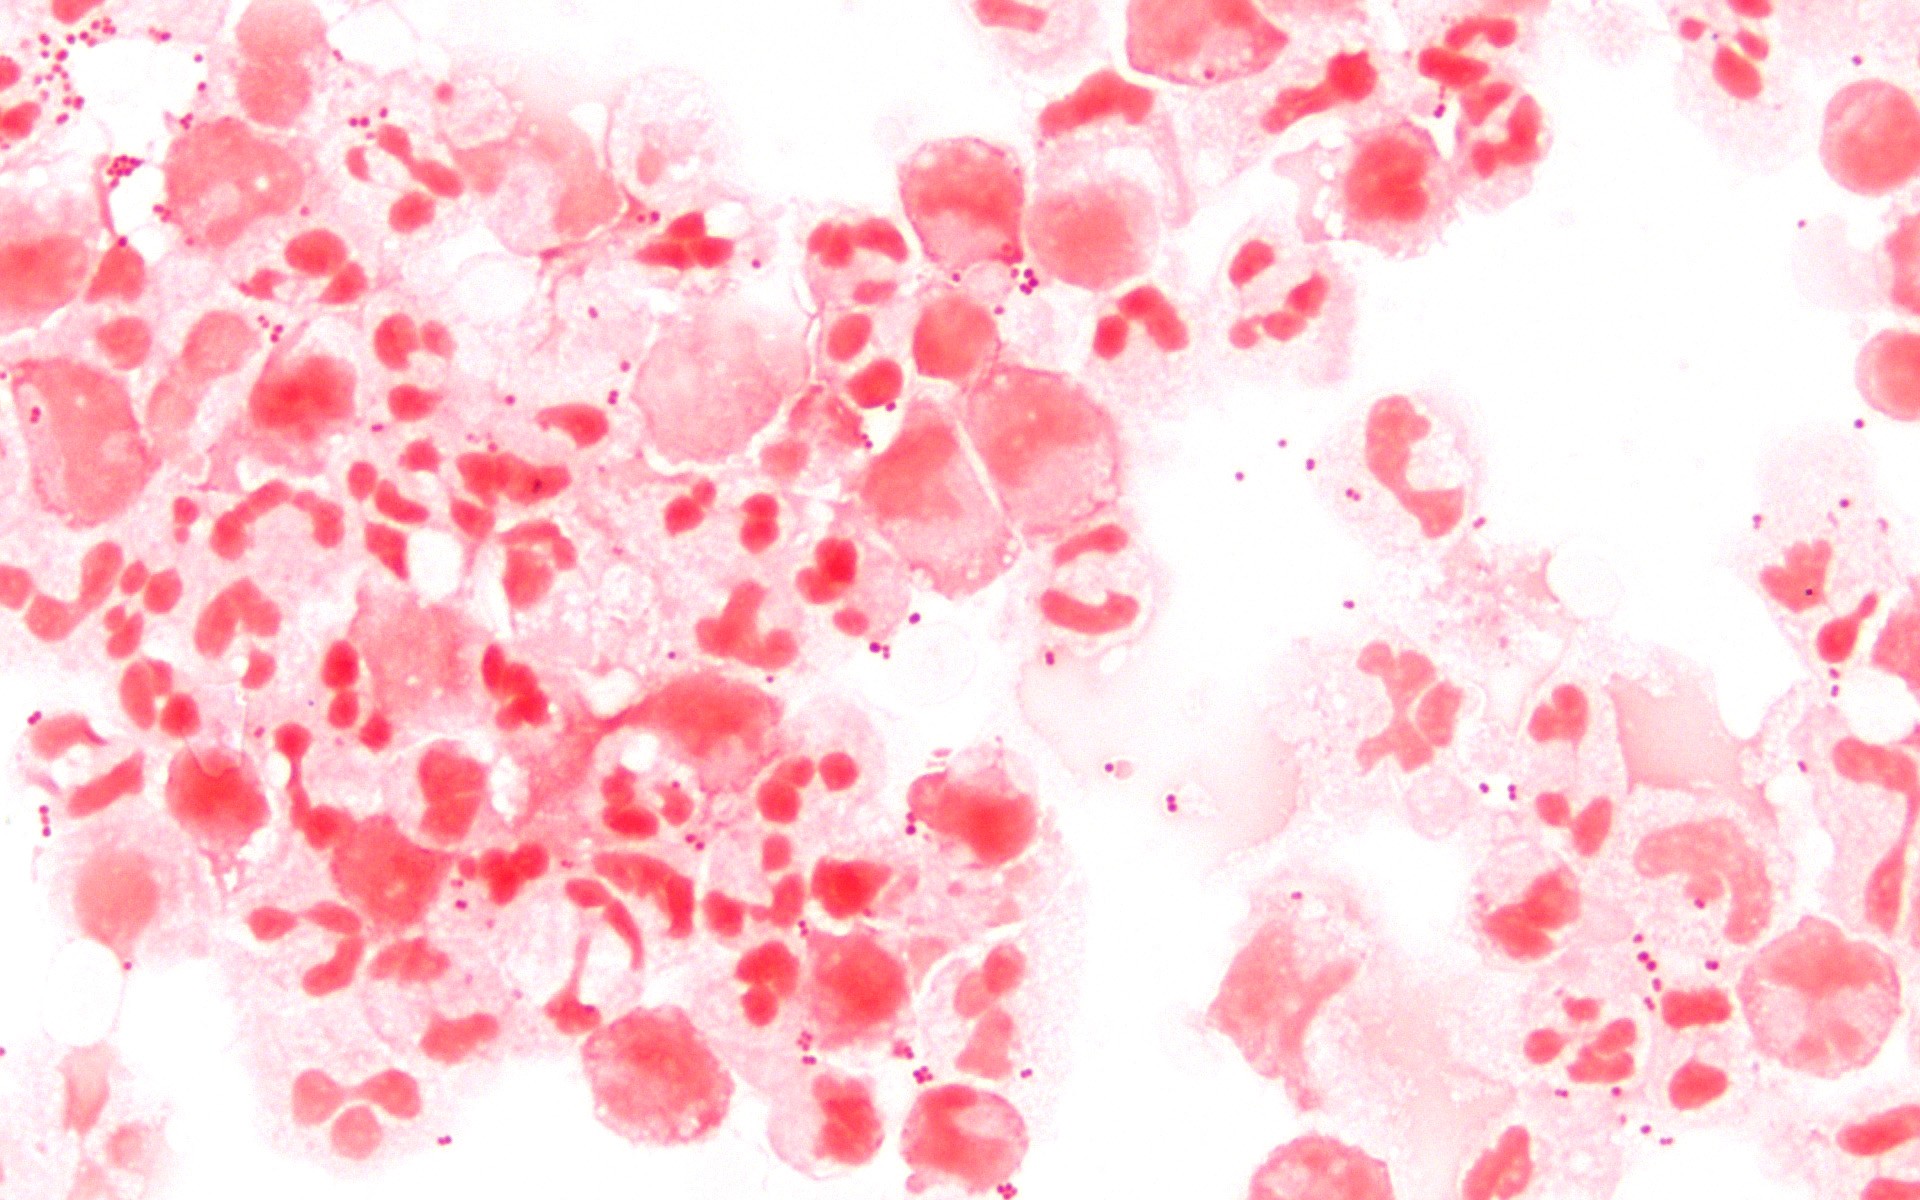

Neisseria meningitidis, a bactéria que causa a meningite meningocócica.

Wikimedia